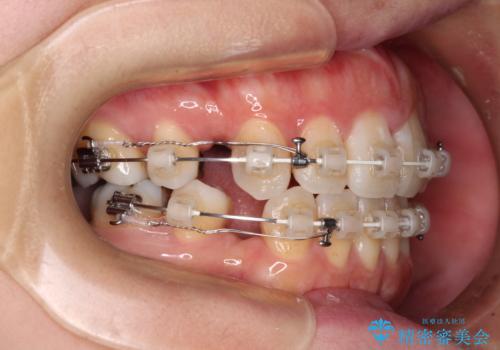

出っ歯と奥歯の欠損 ワイヤー矯正とインプラント治療

- 口元の突出感と奥歯の欠損を気にして来院された患者様です。

口元の突出感改善には、上下左右の第一小臼歯4本を抜歯し、奥歯の欠損部には矯正治療の途中でインプランを埋入していくこととしました。

矯正治療の後半にインプラント埋入を行うことで、トータルの治療期間を短縮することができました。